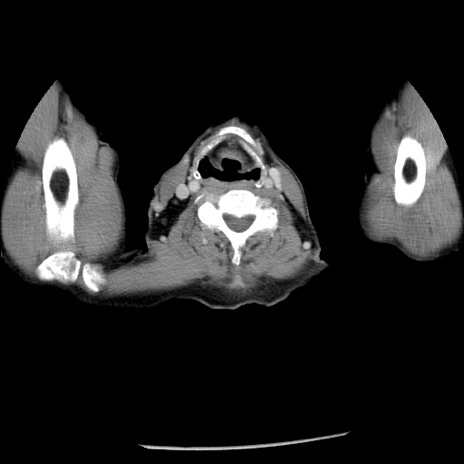

冠状断像

【症例】80歳代男性

【主訴】嘔吐

【現病歴】昨晩2回嘔吐あり、今朝になっても嘔吐あり。来院。

【既往歴】胃潰瘍

【身体所見】意識清明、BT 37.6℃、BP 166/95mmHg、HR 100bpm、SpO2 97%、腹部:平坦・軟、腸蠕動音聴取良好、圧痛なし。

【データ】WBC 21900、CRP 1.46